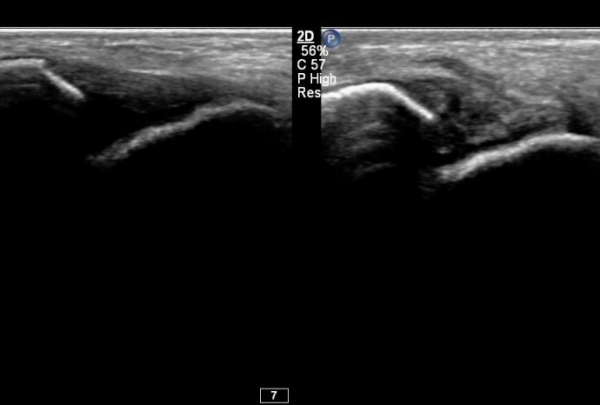

°ÇÃø°ú ºñ±³Çϸé È¯ÃøÀÇ º´Àû ¼Ò°ßÀÌ ¶Ñ·ÈÇÏ´Ù(»çÁø 7).

Àü°ÅºñÀδë Á¾´Ü¸é°Ë»ç¿¡¼­  Àú¿¡ÄÚ ºÎÁ¾ÀÌ °¨¼ÒÇϰí ÀδëÀÇ ¿¡ÄÚ°¡ Áõ°¡µÇ¾ú´Ù(»çÁø 2, 3, 4).

Àü°ÅºñÀδë Ⱦ´Ü¸é°Ë»ç¿¡¼­ Àü°Åºñ ÀÎ´ë ¾ÕÂÊ ºÎÀ§ÀÇ °æ¹ÌÇÑ Àú¿¡ÄÚ ºÎÁ¾ÀÌ °üÂûµµ´Ï´Ù(»çÁø 5).